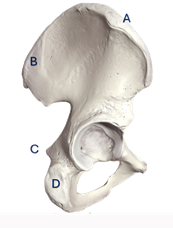

Q1. The highlighted structure in the provided image articulates with which bone?

Q2. Through which of the following foramina does the nerve supplying the muscles of mastication pass?

- A

- B

- C

- D

Answer – C

Q11. The muscle that contributes to both hip and knee extension originates from which of the following structures?

Answer – B